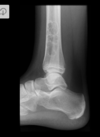

Bico talar

Coalizão calcaneonavicular.